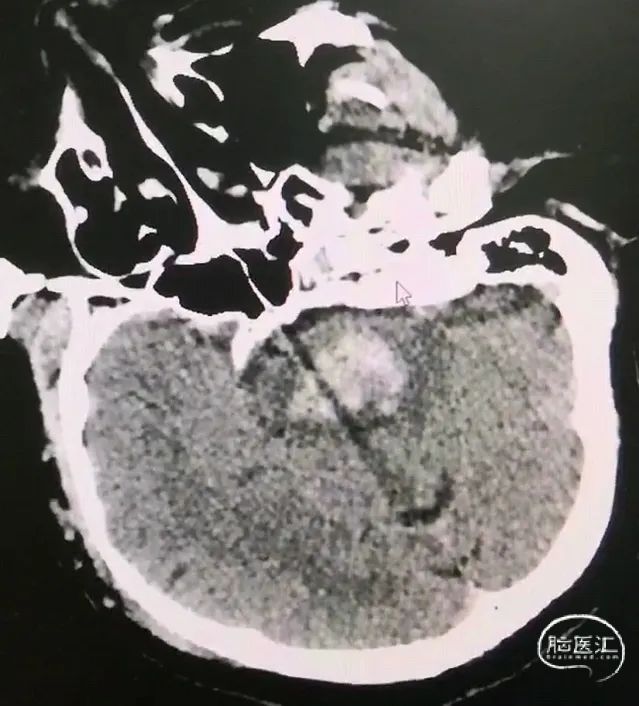

CT扫描后测算脑干血肿穿刺靶点及路径

脑干血肿引流管经大脑脚入中脑

引流管穿经中脑血肿

引流管准确到达靶点